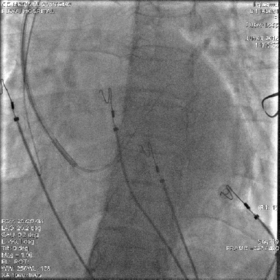

最终影像

AP

LAO

RAO